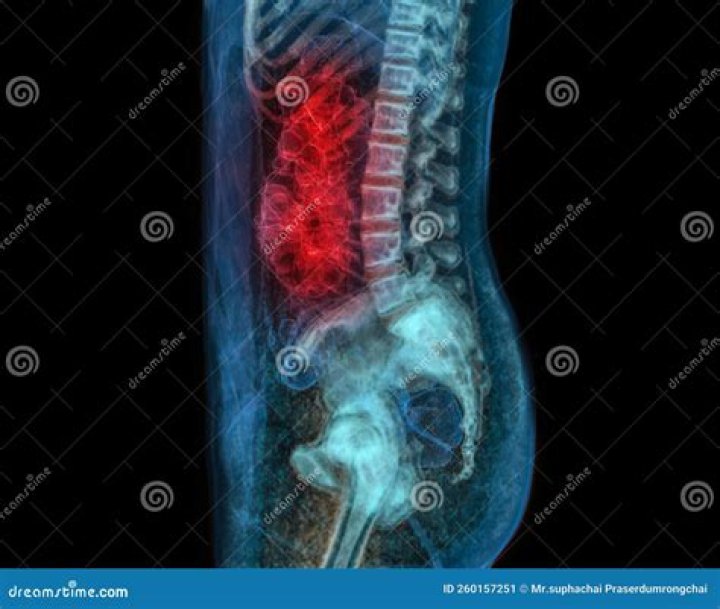

CT scan. Computed tomography (CT) scans can be used in a few ways to help detect colorectal cancer, find signs of cancer in other areas of the body, or determine how well cancer treatment is working.

Early colorectal cancer can be subtle on CT scans showing only mild wall thickening, small polyps, or subtle lymph nodes in atypical draining location. Identifying these lesions on CT scan performed for nonspecific symptoms can help identify interval CRC and improve patient outcome.